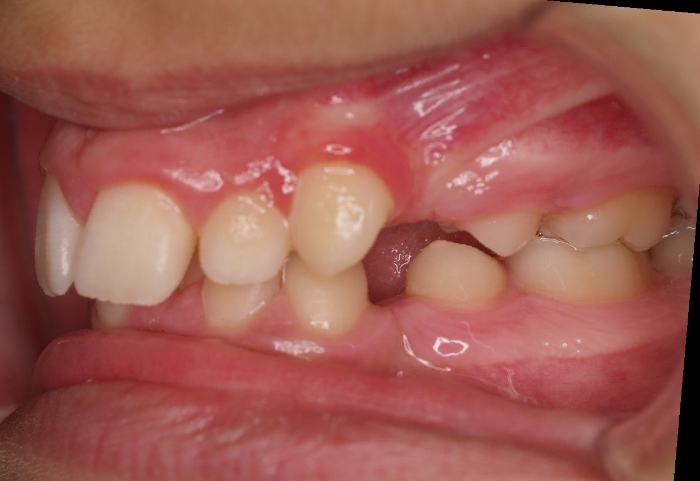

La paciente O.O. acude a nuestra consulta por:

– Canino 13 e incisivo lateral 42 en posición ectópica.

– Canino 23 incluido.

Con lo que decide realizarse un tratamiento de ortodoncia de duración de 24 meses con brackets damon Q.

CASO COMPLETO: